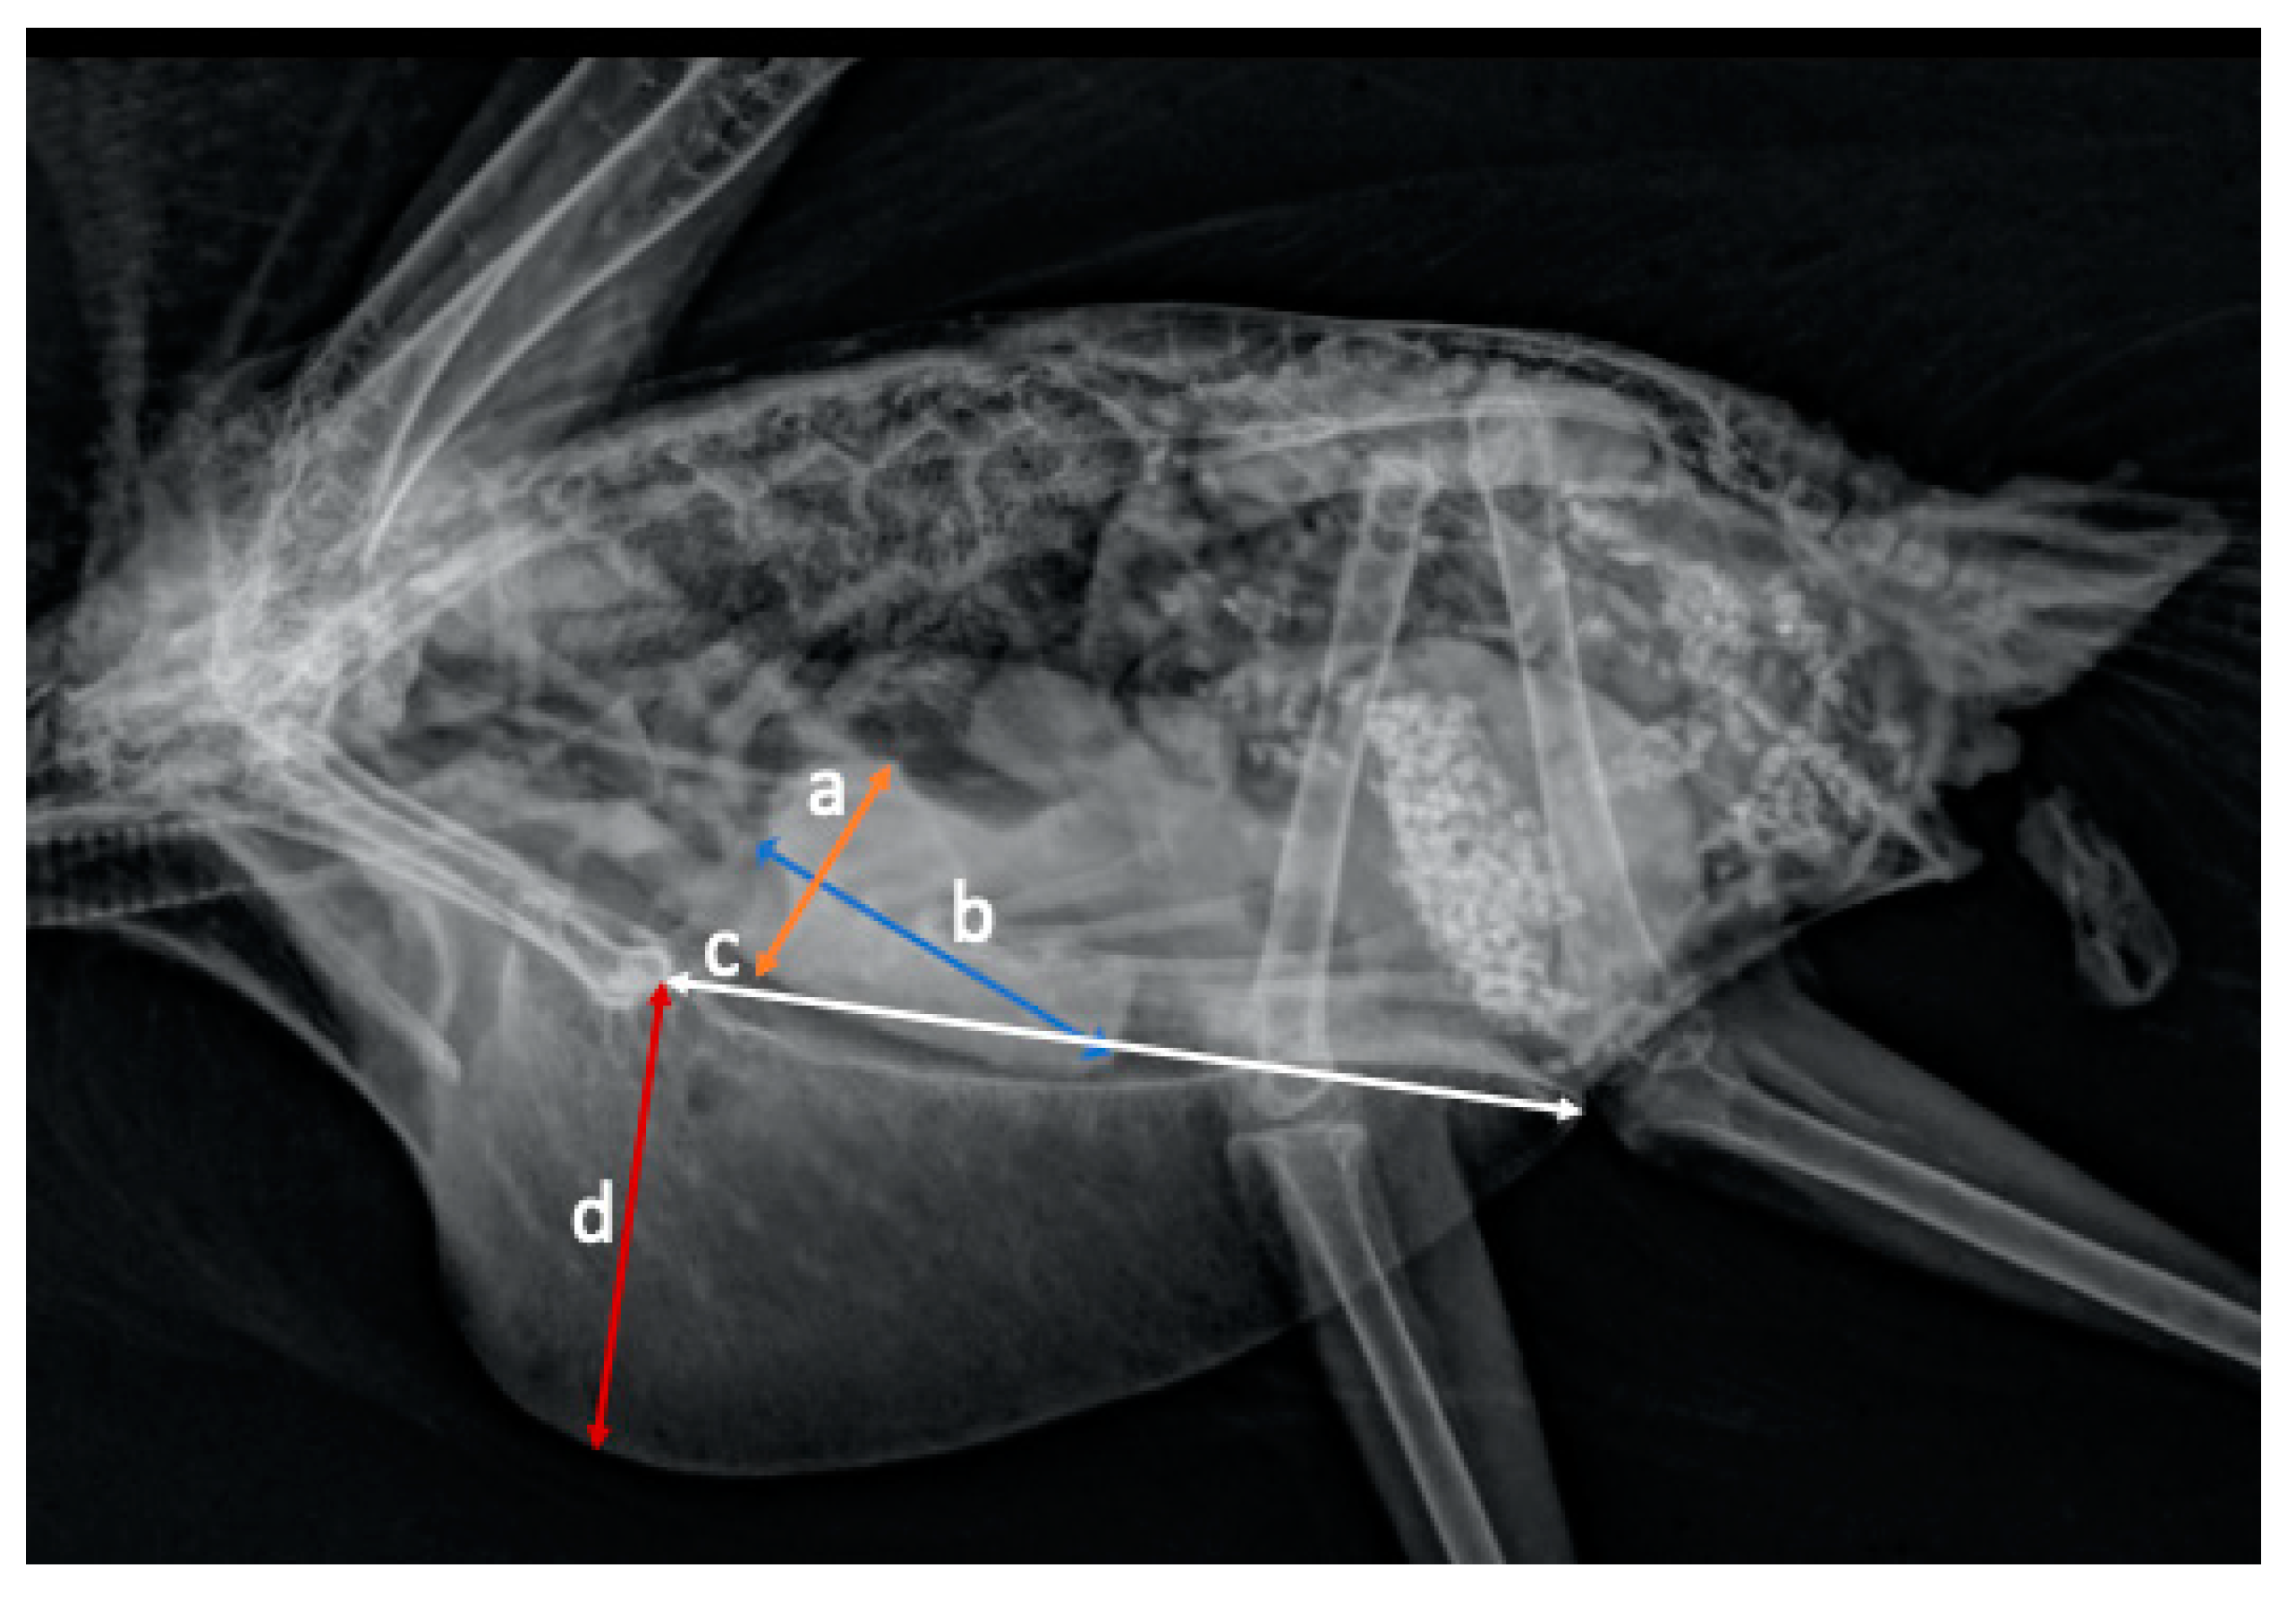

| Mean ± SD | Median | Minimum | Maximum | 90% Confidence Interval | ||

|---|---|---|---|---|---|---|

| Cardiac width (mm) | CW (N = 36) | 21.9 ± 1.3 | 21.5 | 17.8 | 23.6 | 21.0–21.8 |

| Thoracic width (mm) | TW (N = 36) | 36.9 ± 2.1 | 36.6 | 32.5 | 42.1 | 36.3–37.5 |

| Coracoid width (mm) | CoW (N = 36) | 3.3 ± 0.2 | 3.3 | 2.8 | 3.7 | 3.2–3.4 |

| Distance between third and fourth rib (mm) | DR (N = 36) | 6.2 ± 0.6 | 6.3 | 5.00 | 7.3 | 6.0–6.4 |

| Synsacrum width (mm) | SynW (N = 36) | 5.4 ± 0.4 | 5.4 | 4.4 | 6 | 5.3–5.5 |

| Distance clavicle (mm) | DC (N = 33) | 20.6 ± 1.9 | 20.4 | 16.4 | 27.6 | 20.1–21.1 |

| Cardiac length (mm) | CL (N = 36) | 27.6 ± 3.1 | 27.1 | 22.7 | 37.2 | 26.7–28.5 |

| Sternum length (mm) | SL (N = 36) | 51.1 ± 2.3 | 51.0 | 46.7 | 56.3 | 50.4–51.7 |

| Sternum height (mm) | SH (N = 36) | 23.5 ± 2.6 | 24.1 | 15.9 | 27.9 | 22.8–24.2 |